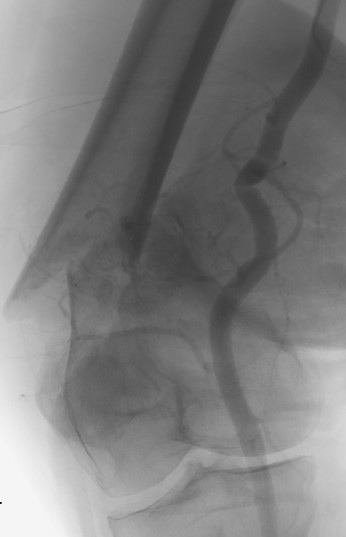

Pre-operative Arterial Embolization

Indications

- renal cell carcinoma

- thyroid carcinoma

Results

- embolisation of RCC metastasis in 107 patients

- success in 96%

- all patients had variable ischemic pain for 2 - 4 day

- 41 cases with embolization prior to surgery compared to 41 cases without

- embolization reduced blood loss, transfusion, and surgical times